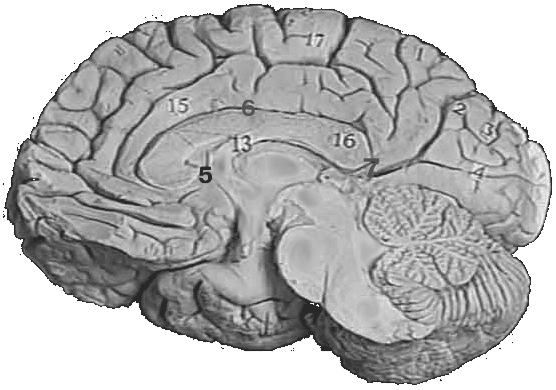

Рис. 3. Медиальная поверхность головного мозга.

1-Precuneus

2-Sulcus parietooccipitalis

3-Cuneus

4-Fissura calcarina

5-Uncus

6-Sulcus corporis collosi

13-Fornix

15-Gyrus cinguli

16-Splenium corporis collosi

17-Lobulus paracentralis